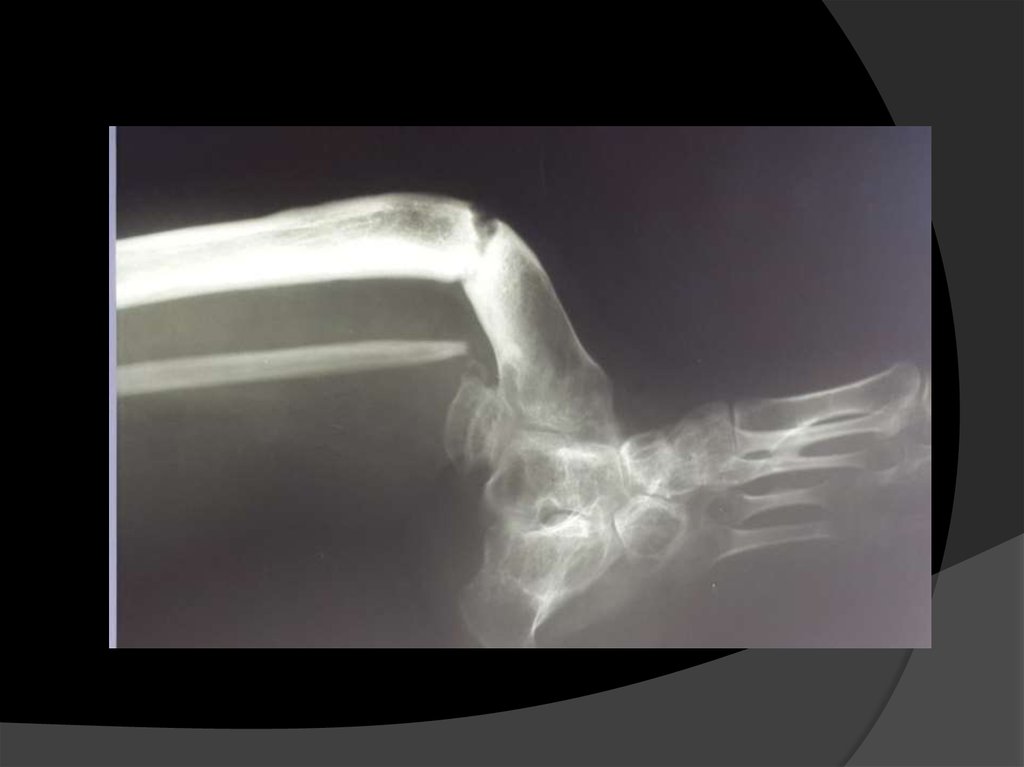

Рентгеновские снимки до операции.

Вопрос: у больной подвывих

голеностопного сустава кнаружи ввиду

дисплазии малоберцовой кости в

н/3.Какую тактику лечения можно

предложить?.